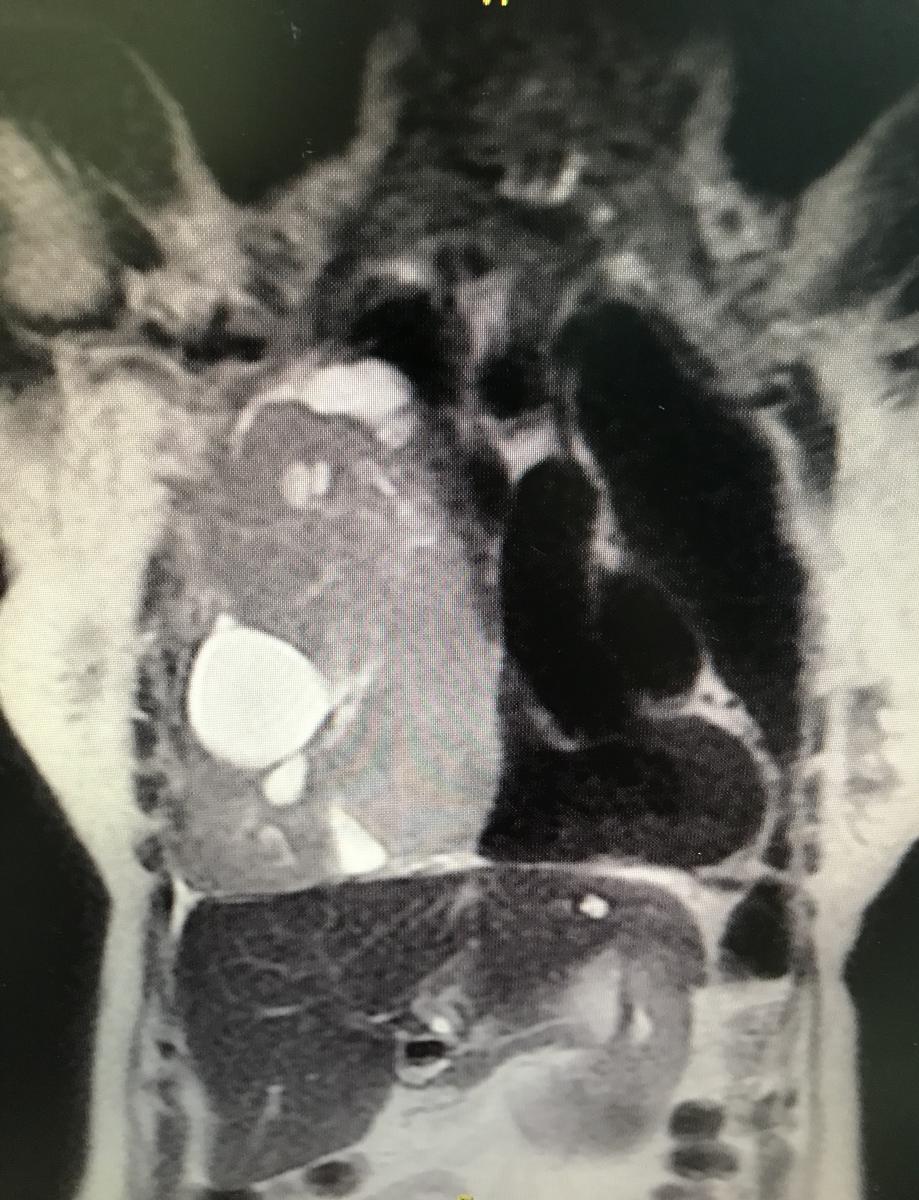

Puncion biopsy was performed with trucut. The Pathological Anatomy report is: fusocellular tumor, DC 34 negative, ASMA positive, S 100 negative, NSE negative, Ki 67 2% suggesting low grade leiomyosarcoma as a diagnosis. Magnetic resonance imaging was performed to visualize the presence of infiltration, mainly of large vessels, and studies for distant disease, without finding images compatible with metastasis (figures 2 and 3).

It is decided together with the patient, relatives, and oncology, the surgical behavior to achieve complete extirpation or the greatest possible resection. Videofibrobronchoscopy was performed first, without evidence of endobronchial lesions. The authors continued with a wide right thoracotomy. Complete resection of the tumor was achieved, along with fragment of diaphragm and pulmonary parenchyma. The tumor was approximately 1.5 kg, compatible with low-grade leiomyosarcomade, with lesion-free resection margins (figure 4). The patient achieved good pulmonary expansion in the immediate postoperative period (figure 5). She recovered in the intensive care unit at the beginning, and then continued in the general ward, with good evolution.